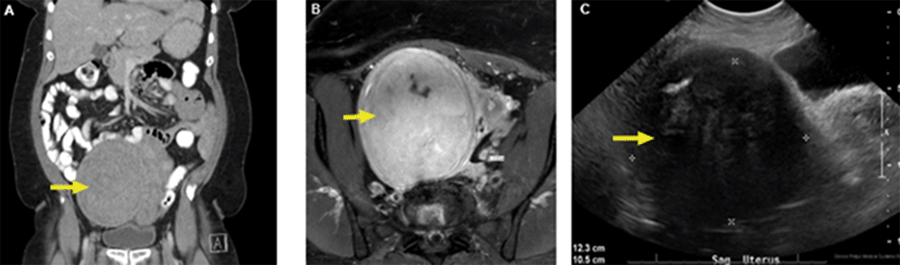

Our patient is a 54-year-old female previously known to surgical service for severe dysphagia secondary to achalasia, treated with Heller myotomy. During the laparoscopic myotomy, the patient was noted to have a large pelvic mass and a significantly enlarged fibroid uterus. She was referred to gynecology and underwent outpatient abdominal axial imaging with computed tomography (CT), magnetic resonance imaging (MRI), and transvaginal ultrasound (Figure 1). All studies indicated the presence of a large pelvic mass of unknown etiology with compression of local structures, as well as a fibroid uterus consistent with prior diagnostic laparoscopy. At the time of diagnosis, she complained of intermittent pelvic and lower abdominal pain but had normal bowel function. The pelvic exam was pertinent for fullness of the left anterior adnexa, and there were no abnormalities on the rectal exam. Laboratory testing confirmed normal cancer antigen 125 (CA125) and carcinoembryonic antigen (CEA) levels.

Figure 1. Imaging Findings of Pelvic Mass. Published With Permission

A) Axial abdominal CT scan; B) axial T2-weighted MRI; and C) transvaginal ultrasound.